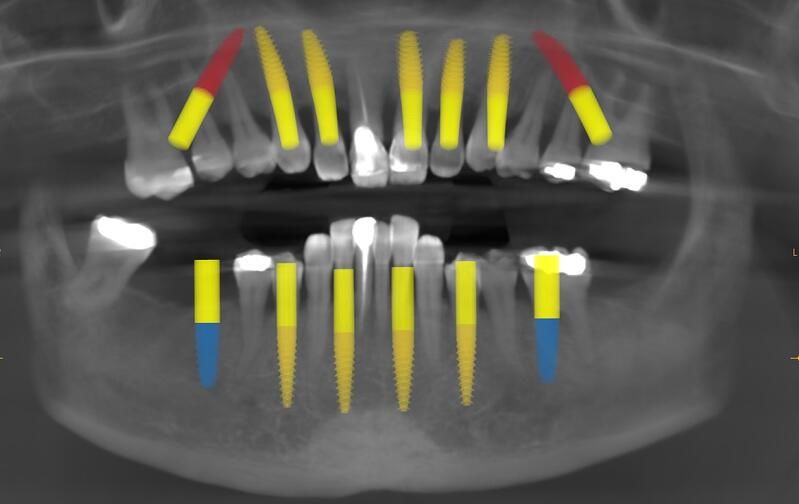

術(shù)前診斷

治 療方案